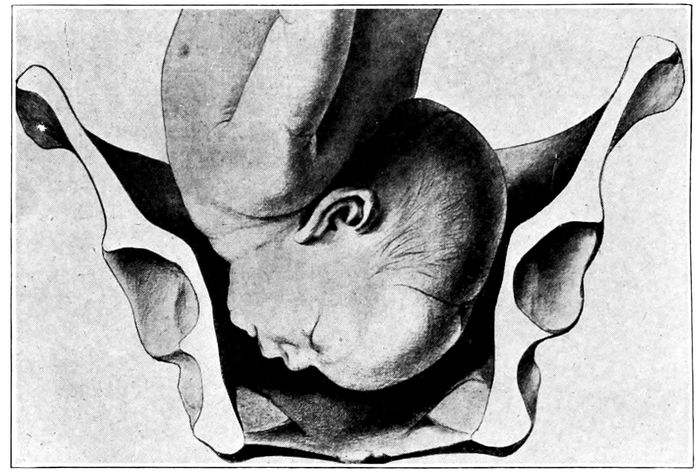

Fig. 21.—Fœtal skulls showing sutures. Note the differences between the anterior and posterior fontanelles. (Eden.)